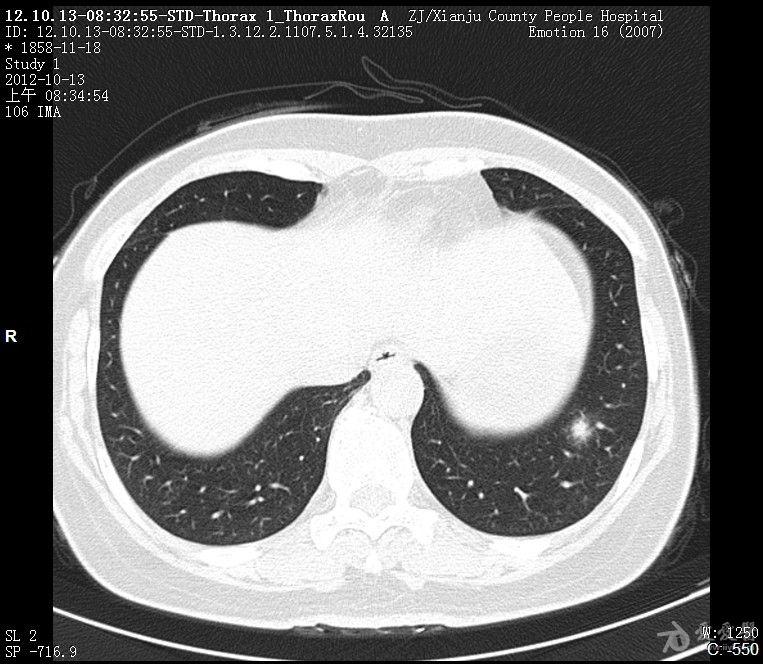

患者无吸烟史,ct提示:左肺下叶后基底段小结节,境界尚清,大小6乘以5mm